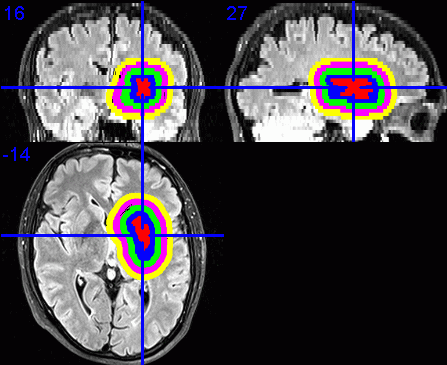

9. Visualisation of dilated VOIs

To visualise the dilated VOIs using MRIcron, I suggest first enabling the

point in section 6 above.

Load the required base images, e.g., the FLAIR images.

Select Overlay / Add. Change the Files of type: to VOIs and

-

dilated band. The VOI filenames start with a 1, 2, 3, ... depending on the

displayed in a different colour.

Click on the centre of the lesion to obtain the required view of the VOIs in

- Select File / Save as Bitmap to save this view as an image that